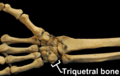

Triquetral bone

The left triquetal bone